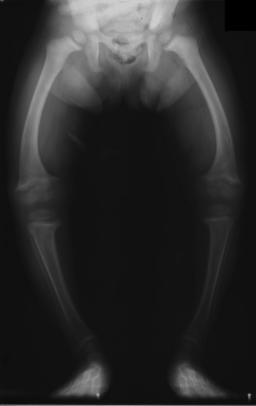

Goblins make no beautiful things, but many clever ones. They are inventive. But they tend to invent things that it would be better if they weren’t invented like weapons for killing lots of people and instruments of torture. We don’t get a good description of what a goblin looks like here but in the Lord of the Rings we hear that they are squint eyed and bow legged. This is reminiscent of the rickets ridden industrial workers who rarely saw the sun that must have been a common sight when Tolkien was growing up. So the goblins, later rebranded as orcs, are inspired by the workers he saw as a boy